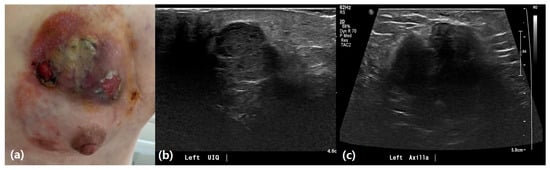

3.2. Ultrasound Features